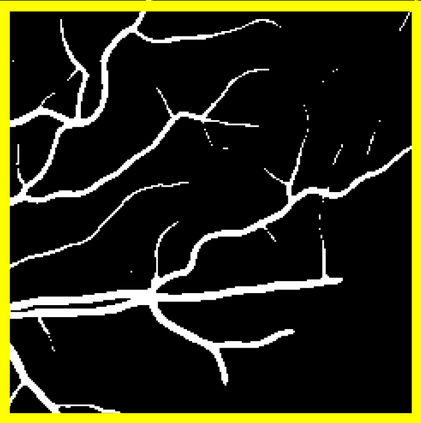

Blood vessel segmentation is crucial for many diagnostic and research applications. In recent years, CNN-based models have leaded to breakthroughs in the task of segmentation, however, such methods usually lose high-frequency information like object boundaries and subtle structures, which are vital to vessel segmentation. To tackle this issue, we propose Boundary Enhancement and Feature Denoising (BEFD) module to facilitate the network ability of extracting boundary information in semantic segmentation, which can be integrated into arbitrary encoder-decoder architecture in an end-to-end way. By introducing Sobel edge detector, the network is able to acquire additional edge prior, thus enhancing boundary in an unsupervised manner for medical image segmentation. In addition, we also utilize a denoising block to reduce the noise hidden in the low-level features. Experimental results on retinal vessel dataset and angiocarpy dataset demonstrate the superior performance of the new BEFD module.